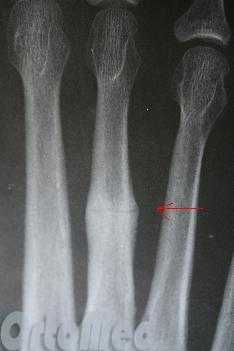

В момент травмы возникает резкая боль, появляется припухлость в результате кровоподтека. Диагноз уточняется путем рентгенологического обследования. Выявлять симптом крепитации у артистов балета не следует, ибо это вызывает смещение отломков и наносится дополнительная травма мягким тканям, окружающим отломки. Чаще наблюдается перелом фаланги V пальца стопы.

Клинически выявляется припухлость по латеральному краю стопы, резкая болезненность при пальпации плюсневой кости, положительный симптом Якобсона (резкая боль при надавливании на подошвенную поверхность головки поврежденной плюсневой кости). Рентгенологически уточняется вид перелома и степень смещения отломков.